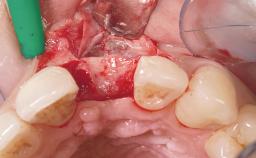

A 33-year-old female patient presented with an upper left central incisor that required extraction after a failed endodontic therapy. The tooth had been traumatized when the patient was a teenager and had undergone several endodontic treatments, including two apicectomy procedures. The patient was in good health and did not smoke. Clinical examination showed that the patient had a high lip line. In full smile, the gingival margins of the upper teeth were visible to the first molars. The gingival margins of central incisors 11 and 21 were only just showing. Examination of tooth 21 confirmed that the tooth was mobile and had hypererupted by 1 mm.